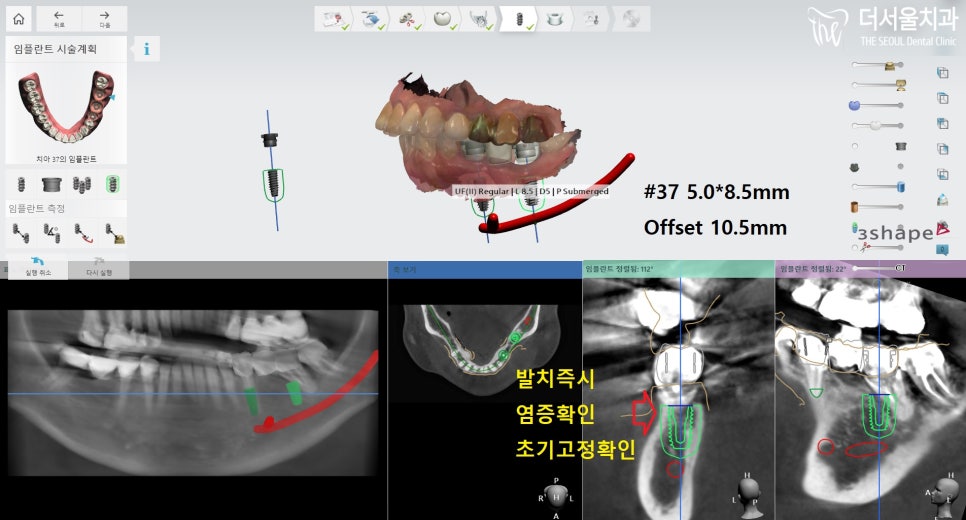

37번 어금니 를 보면,

정말 심각한 상황이었다는 것을

알 수 있죠?

발치 전 컴퓨터 분석을 통해

임플란트 식립 계획을

수립하였는데요.

다행스럽게도 뼈이식을

진행하지 않아도 되었기에

발치 즉시 염증 확인 및

제거하는 과정이 필요했습니다.

의료진이 꼼꼼히 확인 후,

염증이 남아있지 않도록

소독을 통해 깔끔히 처리했습니다.